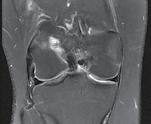

Schatzker III, Osteosinteză cu șuruburi percutană

Schatzker VI, Reducere sângerândă și osteosinteză cu 2 plăci

fracturilor cu separare sau înfundare a platourilor tibiale, precum și a leziunilor de părți moi asociate ligamentare sau de menisc.

Se practică radiografii standard, examinare CT sau RMN.

Radiografiile se fac în cel puțin 3 incidențe: antero-posterioară, laterală și notch intercondilar.

Incidența antero-posterioară poate decela: o bandă osteoscerotică intensificată, specifică fracturii cu înfundare, separarea unui fragment osos, incongruență articulară femuro-tibială. O înfundare mai mare de 6 mm sau/și o incongruență articulară cu lărgirea acesteia mai mult de 5 mm sunt sugestive pentru leziuni de menisc lateral, ligament colateral lateral sau ligament încrucișat posterior(5). O înfundare sau lărgire articulară mai mare de 8 mm este deseori asociată cu o leziune de menisc medial(6).

În baza examenului radiologic au fost propuse mai multe clasificări, dar cea mai folosită este cea a lui Schatzker:

Schatzker I: fracturi cu separare hemiplatou extern

Schatzker II: fracturi cu separare și înfundare hemiplatou extern

Schatzker III: fracturi cu înfundare hemiplatou extern

Schatzker IV: fracturi hemiplatou intern

Schatzker V: fracturi hemiplatou extern și intern

Schatzker VI: fracturi cu extensie metafizo-diafizară

Totuși, 10% din fracturile de platou tibial nu pot fi încadrate în clasificarea Schatzker.

CT-ul cu reconstrucție tridimensională sau RMN genunchi relevă mult mai

bine complexitatea fracturii și dau posibilitatea unui planning preoperator superior estimării radiologice clasice(7). CT-ul este mai rapid și mai ușor de făcut, dar RMN decelează mai bine leziunile de menisc sau ligamentare.

În fracturile Schatzker I, fără leziuni de menisc extern asociate este indicată reducerea și osteosinteza percutană cu șuruburi. Dacă leziunea de menisc este evidențiată pe RMN, se poate opta pentru reducere și osteosinteză percutană cu șuruburi asociată cu artroscopie(12), având rol de control al reducerii și curativ pentru leziunea de menisc, sau reducere deschisă și fixare internă cu placă și șuruburi.

La pacienții tineri cu fracturi Schatzker tip II și III se poate opta pentru reducere și osteosinteză percutană cu șuruburi asociată cu artroscopie. O altă variantă este cu grefă osoasă și reducere deschisă cu fixare internă cu placă și șuruburi. Controlul reducerii intraoperator se realizează artroscopic sau cu C arm.